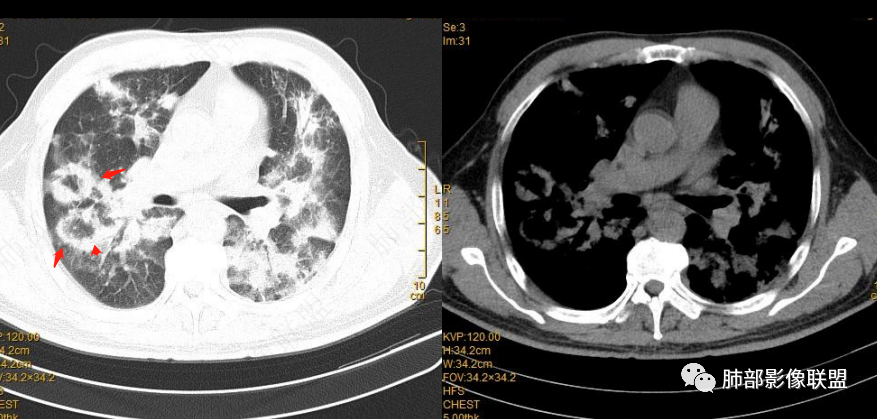

2022.2.17CT显示两肺中内带多发结节影、斑片影、条索影,部分病灶侧向融合与胸膜平行。部分病灶沿着支气管血管束分布、其内支气管稍扩张。部分病灶呈反晕征。大部分病灶边界显示清晰,部分病灶周围可见边界不清的GGO。2022.4.12CT显示两肺中内带多发结节影、条索状、条带状高密度影,边界收缩平直凹陷,大部分病灶沿着支气管血管束分布,亦有位于胸膜下侧向融合与胸膜平行的病灶。总体与第一次CT对比两肺病灶明显吸收。